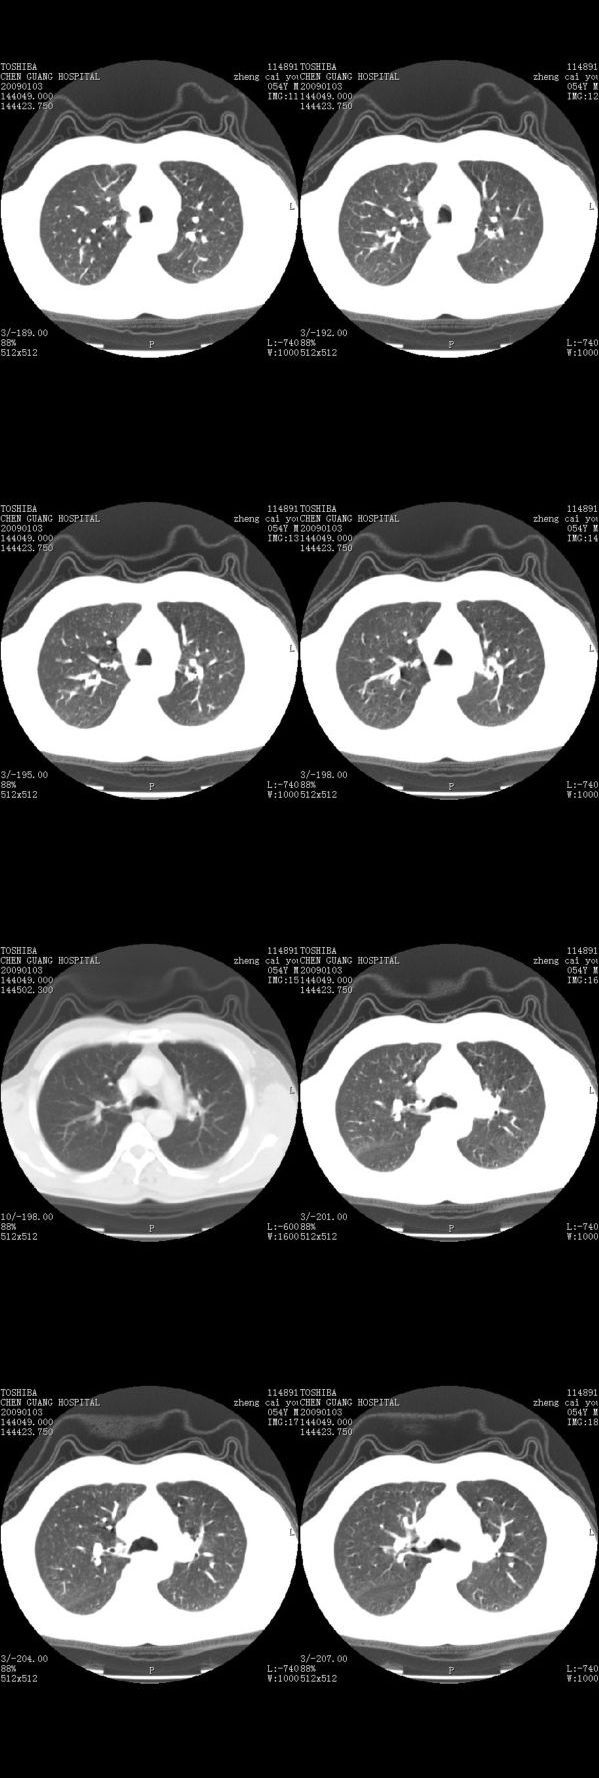

男,54岁,平时有吸烟后咳嗽、咯痰史,因右侧胸部(腋窝下)疼痛来检查平片,见右下肺动脉干起始处处结节,后到同学处做了平扫及增强。请各位老师帮忙看一下,不甚感谢!!!!!

顺序确实有点乱,不过在右肺上叶后段近气管旁仍可见一结节灶,希望楼主小心观察分析。

右肺上叶前后段支气管夹角处可见一结节影,图像资料不全,不好下结论。